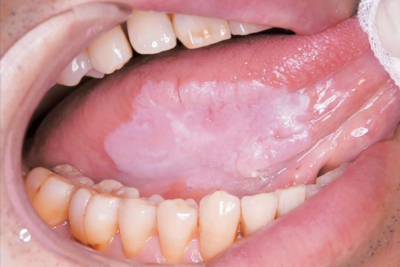

63 歳の男性。舌の異常を主訴として来院した。舌縁部に接触痛や硬結を伴わない病変を認める。初診時の口腔内写真を別に示す。

確定診断に必要な検査はどれか。1つ選べ。

d. 部分(切開) 生検